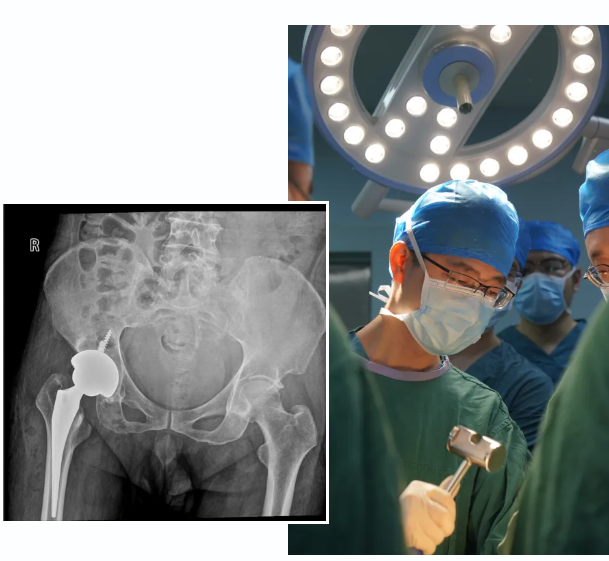

术中,杨德金发现

患者关节僵硬、畸形

增生非常明显

像豆腐渣一样

一碰就碎

杨德金层次分明地进行着

显露、分离

松解、清理

将原本面目全非的髋关节

完整地还原出了

原始的解剖轮廓

后进行扩髓、打磨

试模等系列规范标准化的操作

手术非常成功

术后复查关节位置满意